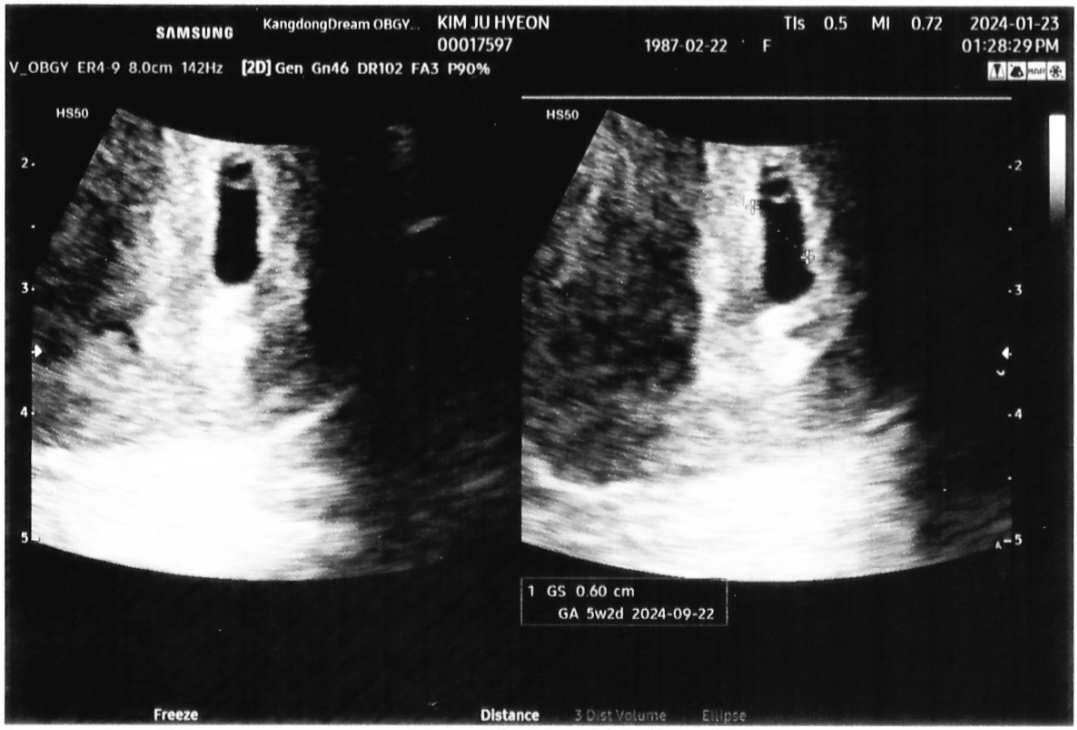

5주차 초음파 보고왔어요~~

막생 12/15일인데 1월15일에 갔더니 왜케 일찍왔냐구 혼났어요ㅋㅋ 피검사 결과 245나왔었고 일주일 뒤에 다시오라셔서 오늘 갔다왔습니다. 5주차 2일이래요 배란이 살짝 늦게됐나봐요 ㅎ 벌써 부터 일주일이 1년 처럼 느껴지는데 걱정쟁이라 어쩌쥬ㅋㅋㅋ 글구 전 모양이 왜이리 길쭉한거죠?ㅎㅎ